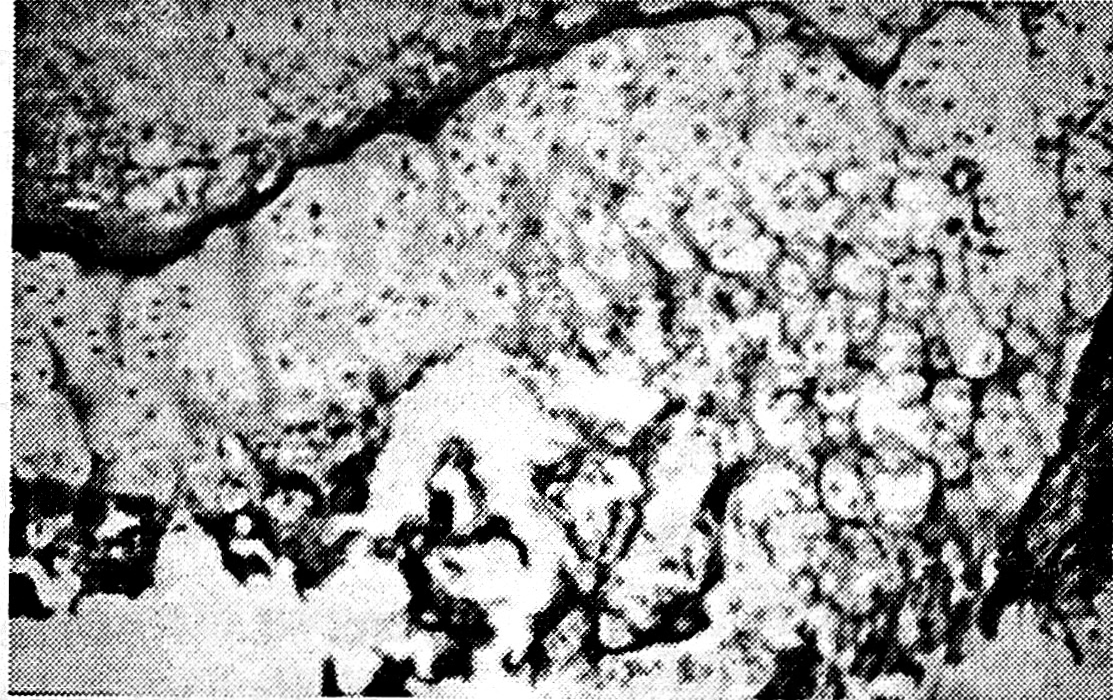

В экспериментах с применением гипсовой повязки (III серия) у 2 щенков на 42-е сутки обнаружено преждевременное замыкание ростковой хрящевой пластинки. Структура зоны роста была замещена костно-фиброзной мозолью. В мозоли, соединяющей отломки эпифиза и метафиза, преобладала малоактивная соединительная ткань (рис. 4). В случаях, когда ростковый хрящ сохранялся, пролиферативные процессы были выражены слабо.

Рис. 4. Гистограмма зоны роста на 42-й день после травмы с последующим лечением гипсовой повязкой (III серия опытов).

Окраска гематоксилином и эозином. Ув. 70.